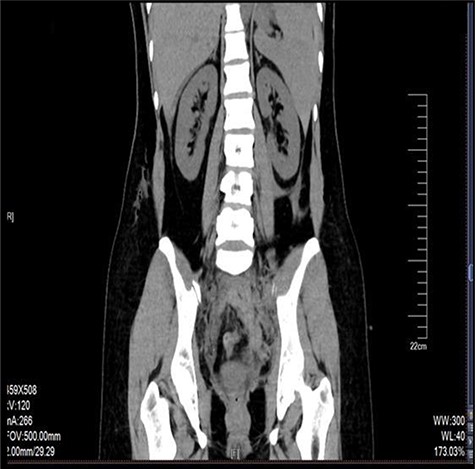

Laparoscopy revealed about 200 ml pelvic free fluid, there was no evidence of active bleeder from pelvic vessels, a retroperitoneal hematoma 6-7 cm in diameter up to the left iliac fossae down to 5 cm above the uterine rectal fossae (Fig. 1). The sigmoid colon and its mesenteric membrane are closely adhered to the left lower abdominal wall. The uterus is anterior full in shape and normal in size, the posterior wall of the uterus partly adhered to the rectum, the fallopian tubes are normal in shape.

The retroperitoneal hematoma appeared stable and no expanding, also no increase in tension. The hemoglobin concentration reexamination showed no significant change. Considering the bleeding has stopped, the trauma surgeon recommended no further incision for the retroperitoneal hematoma after consultation. Digital subtraction angiography (DSA) was done after operation to further confirm no more artery bleeding. DSA revealed the inferior mesenteric artery and the iliac artery were intact (Figs 2 and 3). The patient was placed in the intensive care unit with a angiographic catheter retained for emergency use. They estimated the total blood loss 1500-2000 ml, 200 ml of fresh frozen plasma and 4 units of packed red blood cells were transfused during operation.